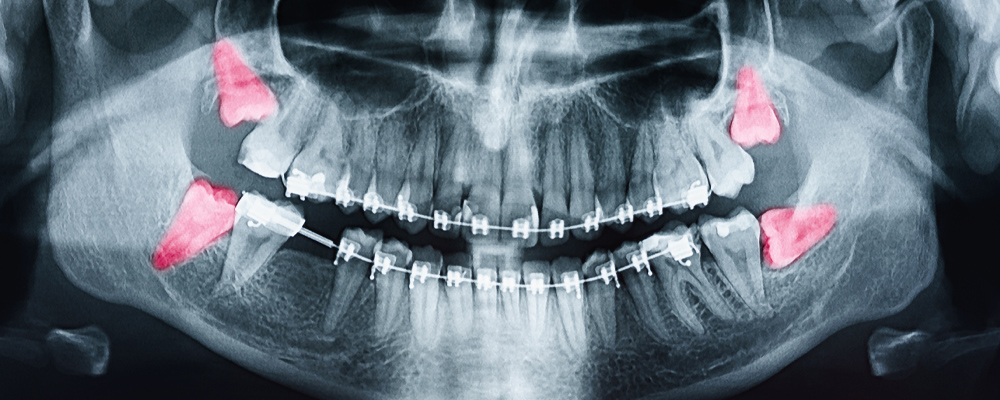

親知らずは真っ直ぐに生えてこないことが多い

昔は親知らずが正しく生えてくる人が過半数を占めていましたが、最近は食生活の変化などの影響により顎が小さく、親知らずが正常(まっすぐ)に生える割合は全体の約10〜30%程度で、残りの約70〜90%は斜め・真横に生えるなど、何らかのトラブルを抱えるケースが多いです。

【最近の親知らずの生え方の傾向】

- 斜めに生える

- 横向きに埋まっている

- 一部だけ歯ぐきから出ている

- 完全に骨の中に埋まっている

この「正常に生えてこない親知らず」が、さまざまな問題を引き起こす原因になります。

② 虫歯・歯周病になるリスクが高い場合

親知らずが斜めに生えていると、歯ブラシが届きにくくなります。その結果、手前の大切な奥歯までむし歯や歯周病になることがあります。特に横向きに埋まっているケースでは、知らないうちに手前の歯の根元が溶けてしまうこともあります。親知らず1本の問題ではなく、「その隣の健康な歯を守るかどうか」という視点が大切です。

③ 噛み合わせや歯並びに影響する場合

親知らずが横向きになっている場合、手前の歯に後ろから押すような力がかかります。親知らずが手前の歯を強く押くことによって、歯並びが悪くなってしまうことがあります。また強い圧力がかかることで、前歯の歯並びに影響を与える可能性もあります。矯正治療後の後戻りを防ぐ観点からも、必要に応じて抜歯をすすめることがあります。